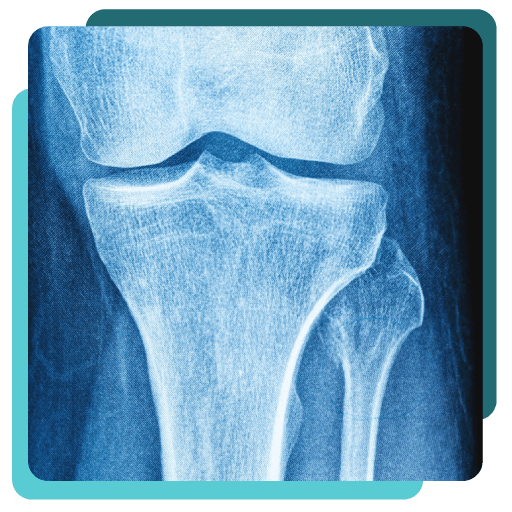

Bone densitometry is a form of x-ray technology used to measure bone loss.

Bone density scanning, also called dual-energy x-ray absorptiometry (DEXA) or bone densitometry, is a form of x-ray technology used to measure bone loss. DEXA is most often used to diagnose osteoporosis, a gradual loss of calcium that causes bones to become thinner, more fragile and more likely to break. It is typically used to measure bone density of the hip and lumbar spine areas.

The DEXA machine produces two X-ray beams, each with different energy levels. One beam is high energy while the other is low energy. The amount of X-rays that pass through the bone is measured for each beam, which will vary depending on the thickness of the bone. Based on the difference between the two beams, the bone density is measured.